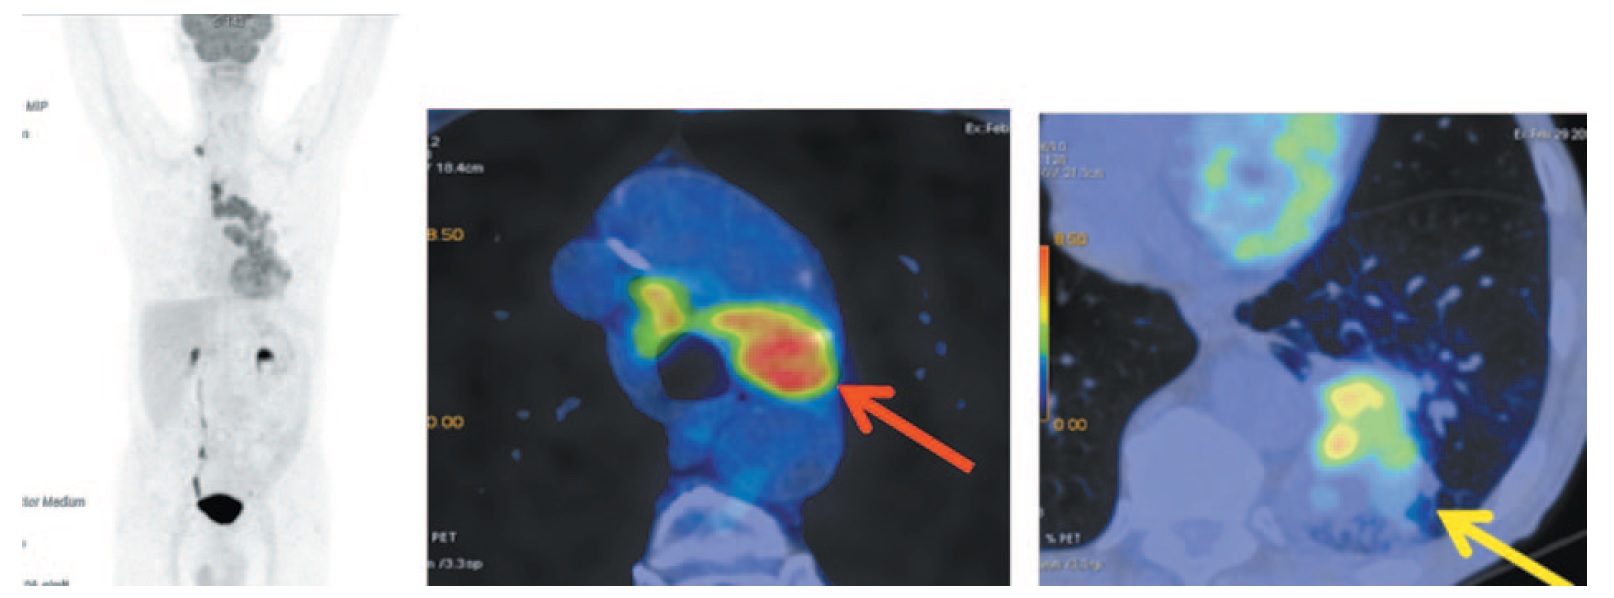

Комбинированная позитронно-эмиссионная и рентгеновская КТ (ПЭТ/КТ) с 18F-фтордезоксиглюкозой (ФДГ): патологическое образование в нижней доле левого легкого S10 размером 41×57×81 мм, SUVmax 10,75. В надключичной области справа определяется увеличенный метаболически активный лимфоузел размером до 14×9 мм, SUVmax 7,82. Увеличены паратрахеальные, бифуркационные, бронхопульмональные лимфоузлы (SUVmax 11,20), лимфоузлы аортопульмонального окна размером до 21×45 мм, SUVmax 10,53. В головном мозге в режиме рентгеновской КТ очаговых образований не выявлено. Экссудативный плеврит слева (рис. 1).

Рис. 1. Больной П., 76 лет, до лечения. На МIP- и аксиальных ПЭТ/КТ-проекциях определяется увеличенный метаболически активный надключичный лимфоузел справа размером до 14×9 мм, SUVmax 7,82. На фоне ателектаза нижней доли левого легкого в S10 визуализируется объемное образование (желтая стрелка), распространяющееся к корню, общим размером до 41×57×81 мм, прилегающее к задней костальной и паравертебральной плевре, с повышенной метаболической активностью ФДГ (SUVmax 10,75). Увеличены паратрахеальные, бифуркационные, бронхопульмональные лимфоузлы (SUVmax 11,20), лимфоузлы аортопульмонального окна размером до 21×45 мм, SUVmax 10,53 (красная стрелка). / Fig. 1. A 76-year-old patient P. before the treatment. MIP and axial PET/CT images show an enlarged metabolically active right supraclavicular lymph node measuring 14×9 mm, SUVmax 7.82. Against the background of atelectasis of the left lower lobe, a tumor mass formation (yellow arrow) is visualized in S10, extending to the root of the lung, with a total size measuring 41×57×81 mm, adjacent to the posterior costal and paraspinal pleura, with increased FDG metabolic activity (SUVmax 10.75). Enlarged paratracheal, bifurcation, bronchopulmonary lymph nodes (SUVmax 11.20) and aortopulmonary window lymph nodes measuring 21×45 mm, SUVmax 10.53 (red arrow) is detected.